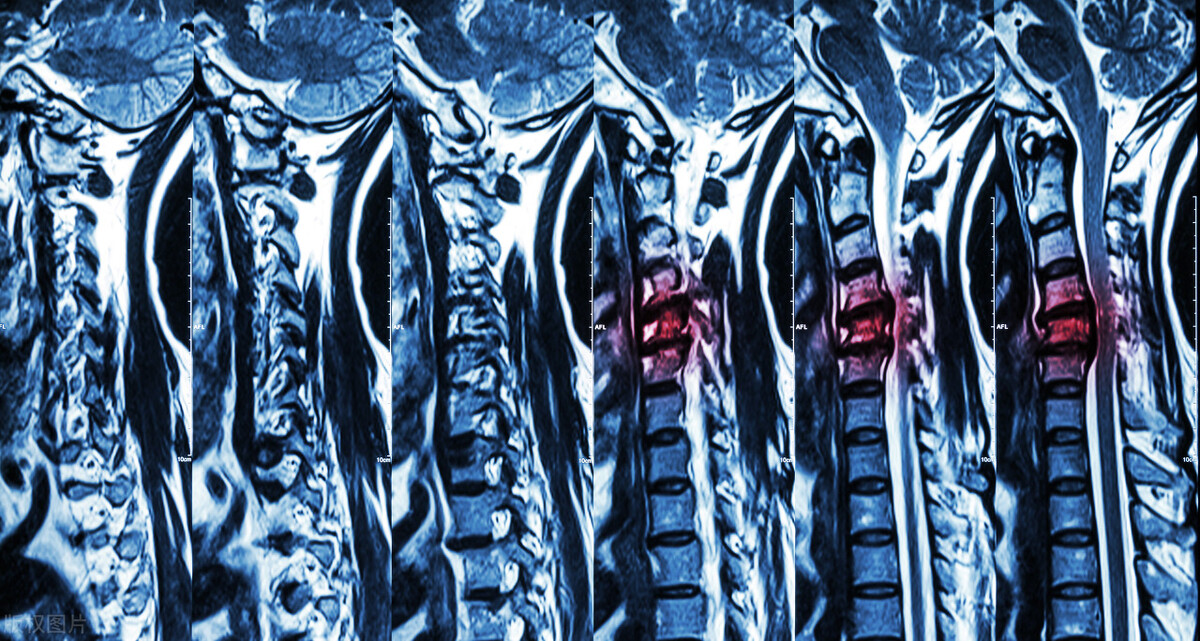

半个月前来问诊,通过核磁检查,显示患者颈椎间盘突出压迫神经。